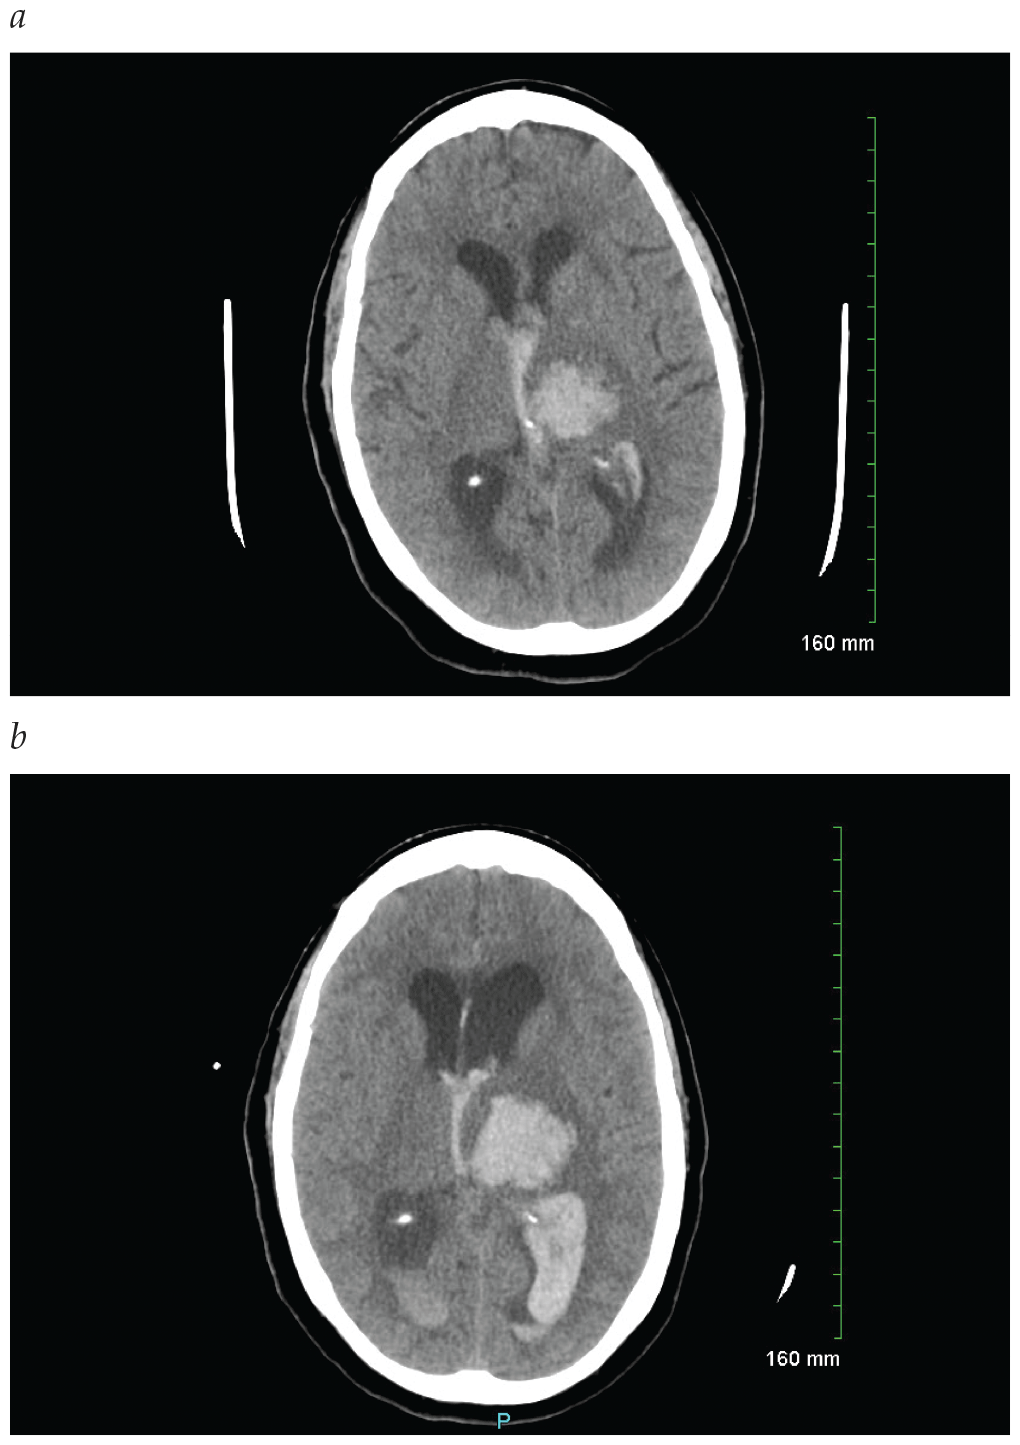

Intracerebral Hemorrhage

• Platelet transfusion is not recommended in the setting of spontaneous ICH for patients who are taking antiplatelet medications.

• Moderate blood pressure control may be better than aggressive blood pressure control in the acute treatment of intracerebral hemorrhage.

• It is important to provide the appropriate reversal agents to patients with novel oral anticoagulant related ICH. These include idarucizumab for reversal of dabigatran, and andexanet alfa for reversal of factor Xa inhibitors such as rivaroxaban, apixaban, and edoxaban.